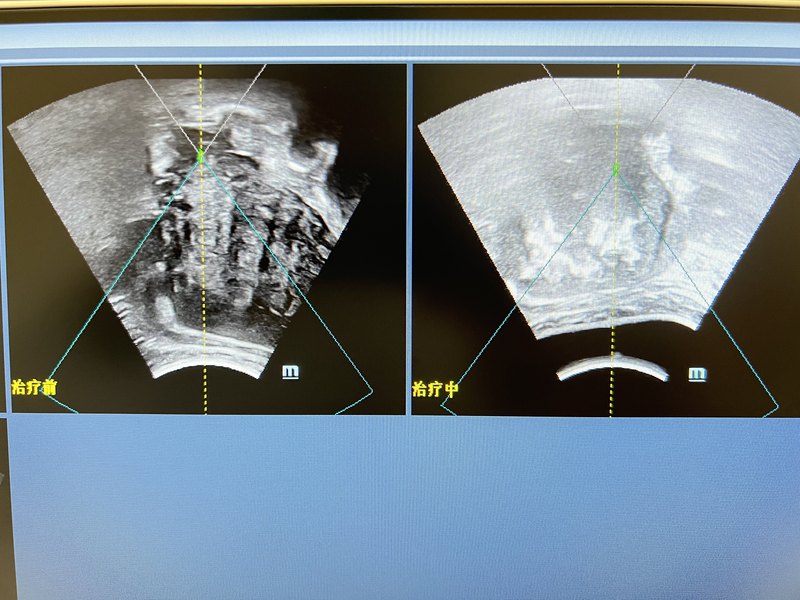

今天海扶治療了兩個同胞,一個來著香港,一個來著澳門,都是大肌瘤,而且是多發(fā),香港和澳門的醫(yī)生都建議手術(shù)治療,開腹子宮切除,患者找到我們醫(yī)院要求海扶治療,上午和下午分別治療了這兩位患者,消融率90%??梢姾7龅对谥委煷蠹×龇矫嫘Ч彩呛芎玫?。